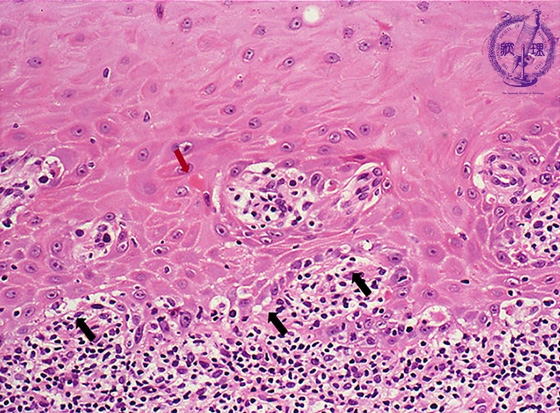

Microscopic finding (HE stain, high-power view):The basal cells show vacuolar change, or hydropic (liquefaction) degeneration (black arrows) and there is cleft formation between the epidermis and papillary dermis. Colloid bodies (degenerating keratinocytes) (red arrow) are seen in the epithelium.